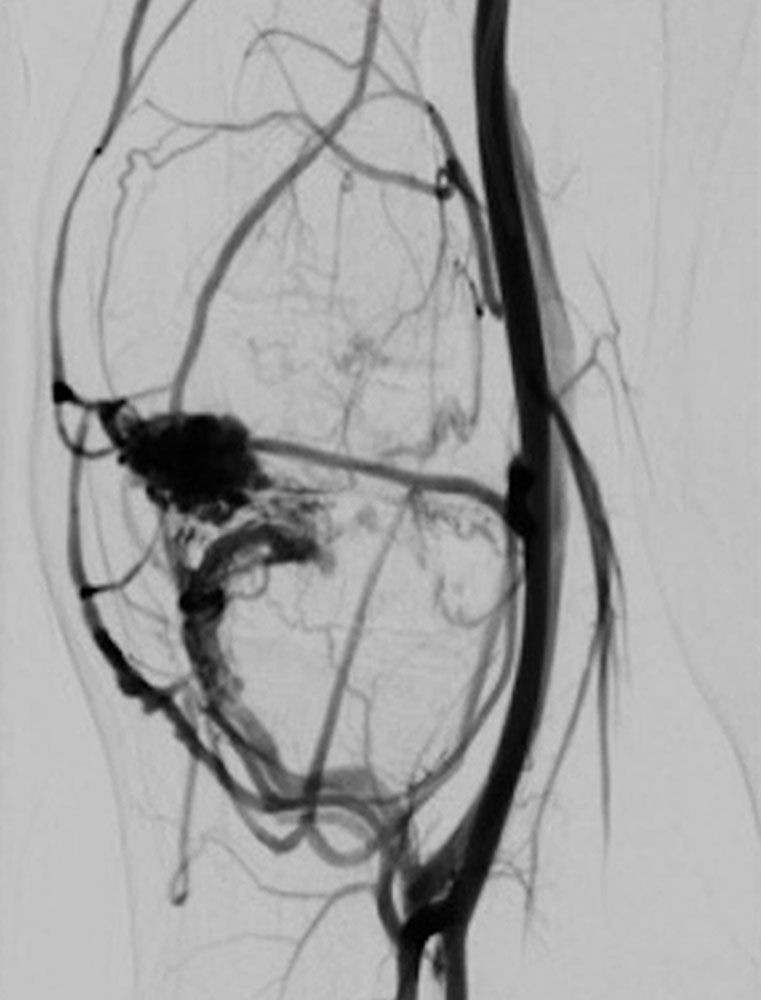

The accompanying vascular malformations do not always occur but, in addition to the increased likelihood of tumor occurrence, are often determinant of the disease course or symptomatology. Relatively characteristic are the often progressive, circumscribed soft tissue changes known as PHOST (PTEN Hamartoma Of Soft Tissue), which histologically present as mixed vascular and soft tissue malformations (capillary, venous and lymphatic malformations) embedded in atypically increased hyperplastic adipose tissue. Concomitant arteriovenous fast-flow malformations are characterized by more spherical, intranidal, or venous “flow-related” aneurysms and frequently recur after treatment.

• If necessary, therapy of vascular malformations, which tend to recur, however, especially in AVM